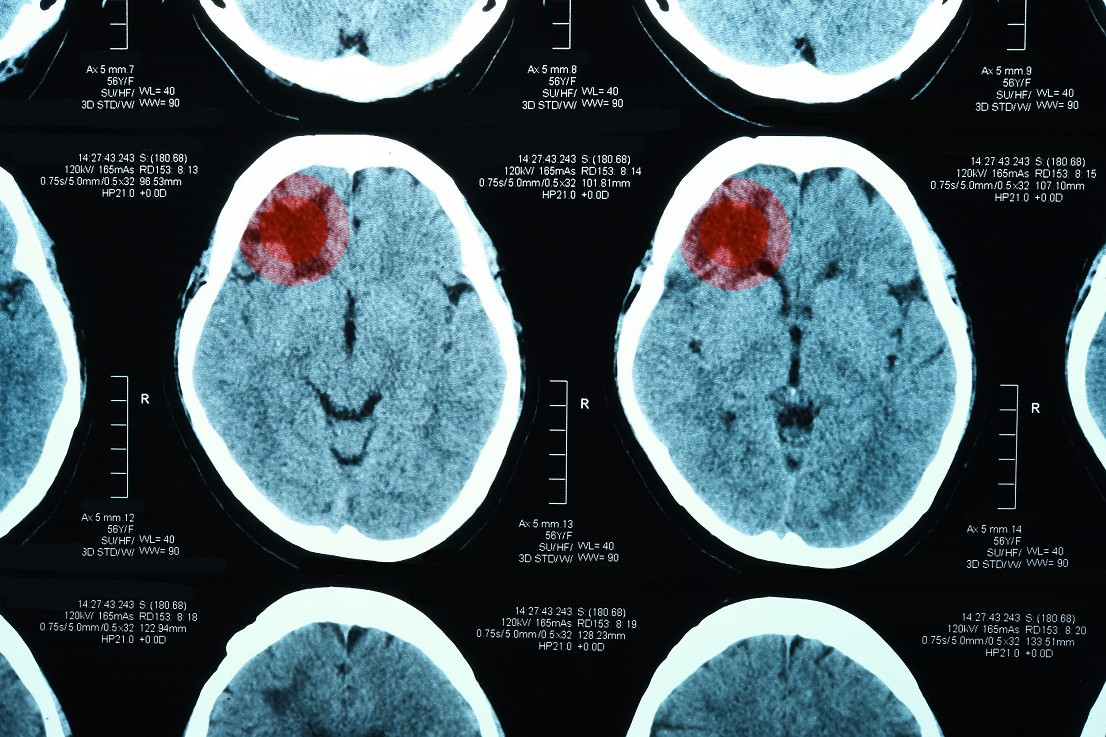

COVID-19 увеличивал риски неблагоприятных исходов при внутримозговом кровоизлиянии

Ученые выяснили, что COVID‐19 существенно увеличивает неблагоприятные исходы у пациентов с внутримозговым кровоизлиянием. Результаты исследования опубликованы в журнале JAHA.

Анализ показал, что у пациентов с внутримозговым кровоизлиянием и положительным тестом на COVID-19 вероятность неблагоприятного исхода повышалась на 68%, риск смерти увеличивался на 51%, а вероятность попадания в хоспис после госпитализации — на 66% в сравнении с участниками с отрицательным исследованием на коронавирусную инфекцию.

Кроме того, сравнив данные о пациентах, госпитализированных до и после начала пандемии, эксперты выяснили, что во время пандемии риск неблагоприятных исходов при внутримозговом кровоизлиянии повышался на 10%, а вероятность смерти – на 5%.

| Анализировали данные 120 тыс. пациентов с внутримозговым кровоизлиянием. Участников разделили на группы в зависимости от результатов тестирования на COVID-19 до и во время пандемии. |

Эксперты подчеркивают, что наличие инфекции COVID-19 существенно увеличивает риски неблагоприятных исходов у пациентов с внутримозговым кровоизлиянием. В свете этих данных, особенно в условиях пандемии, важно усилить меры мониторинга и эффективного лечения этой категории пациентов.